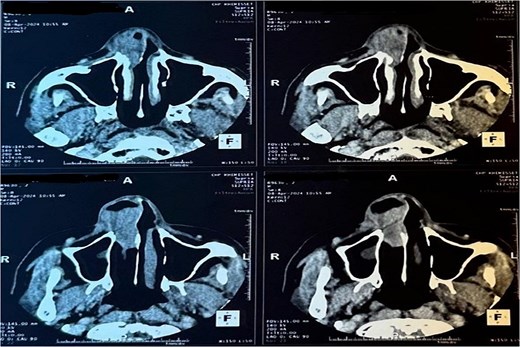

A CT scan revealed a mass centered on the right inferior turbinate, with no bony involvement but a polypoid filling of the right maxillary sinus, raising concern for malignancy (Figs 2 and 3).

Tomography image of the paranasal sinuses in coronal slice with parenchymal window revealing a tumoral-like mass in the right nasal cavity, centered on the right inferior turbinate.